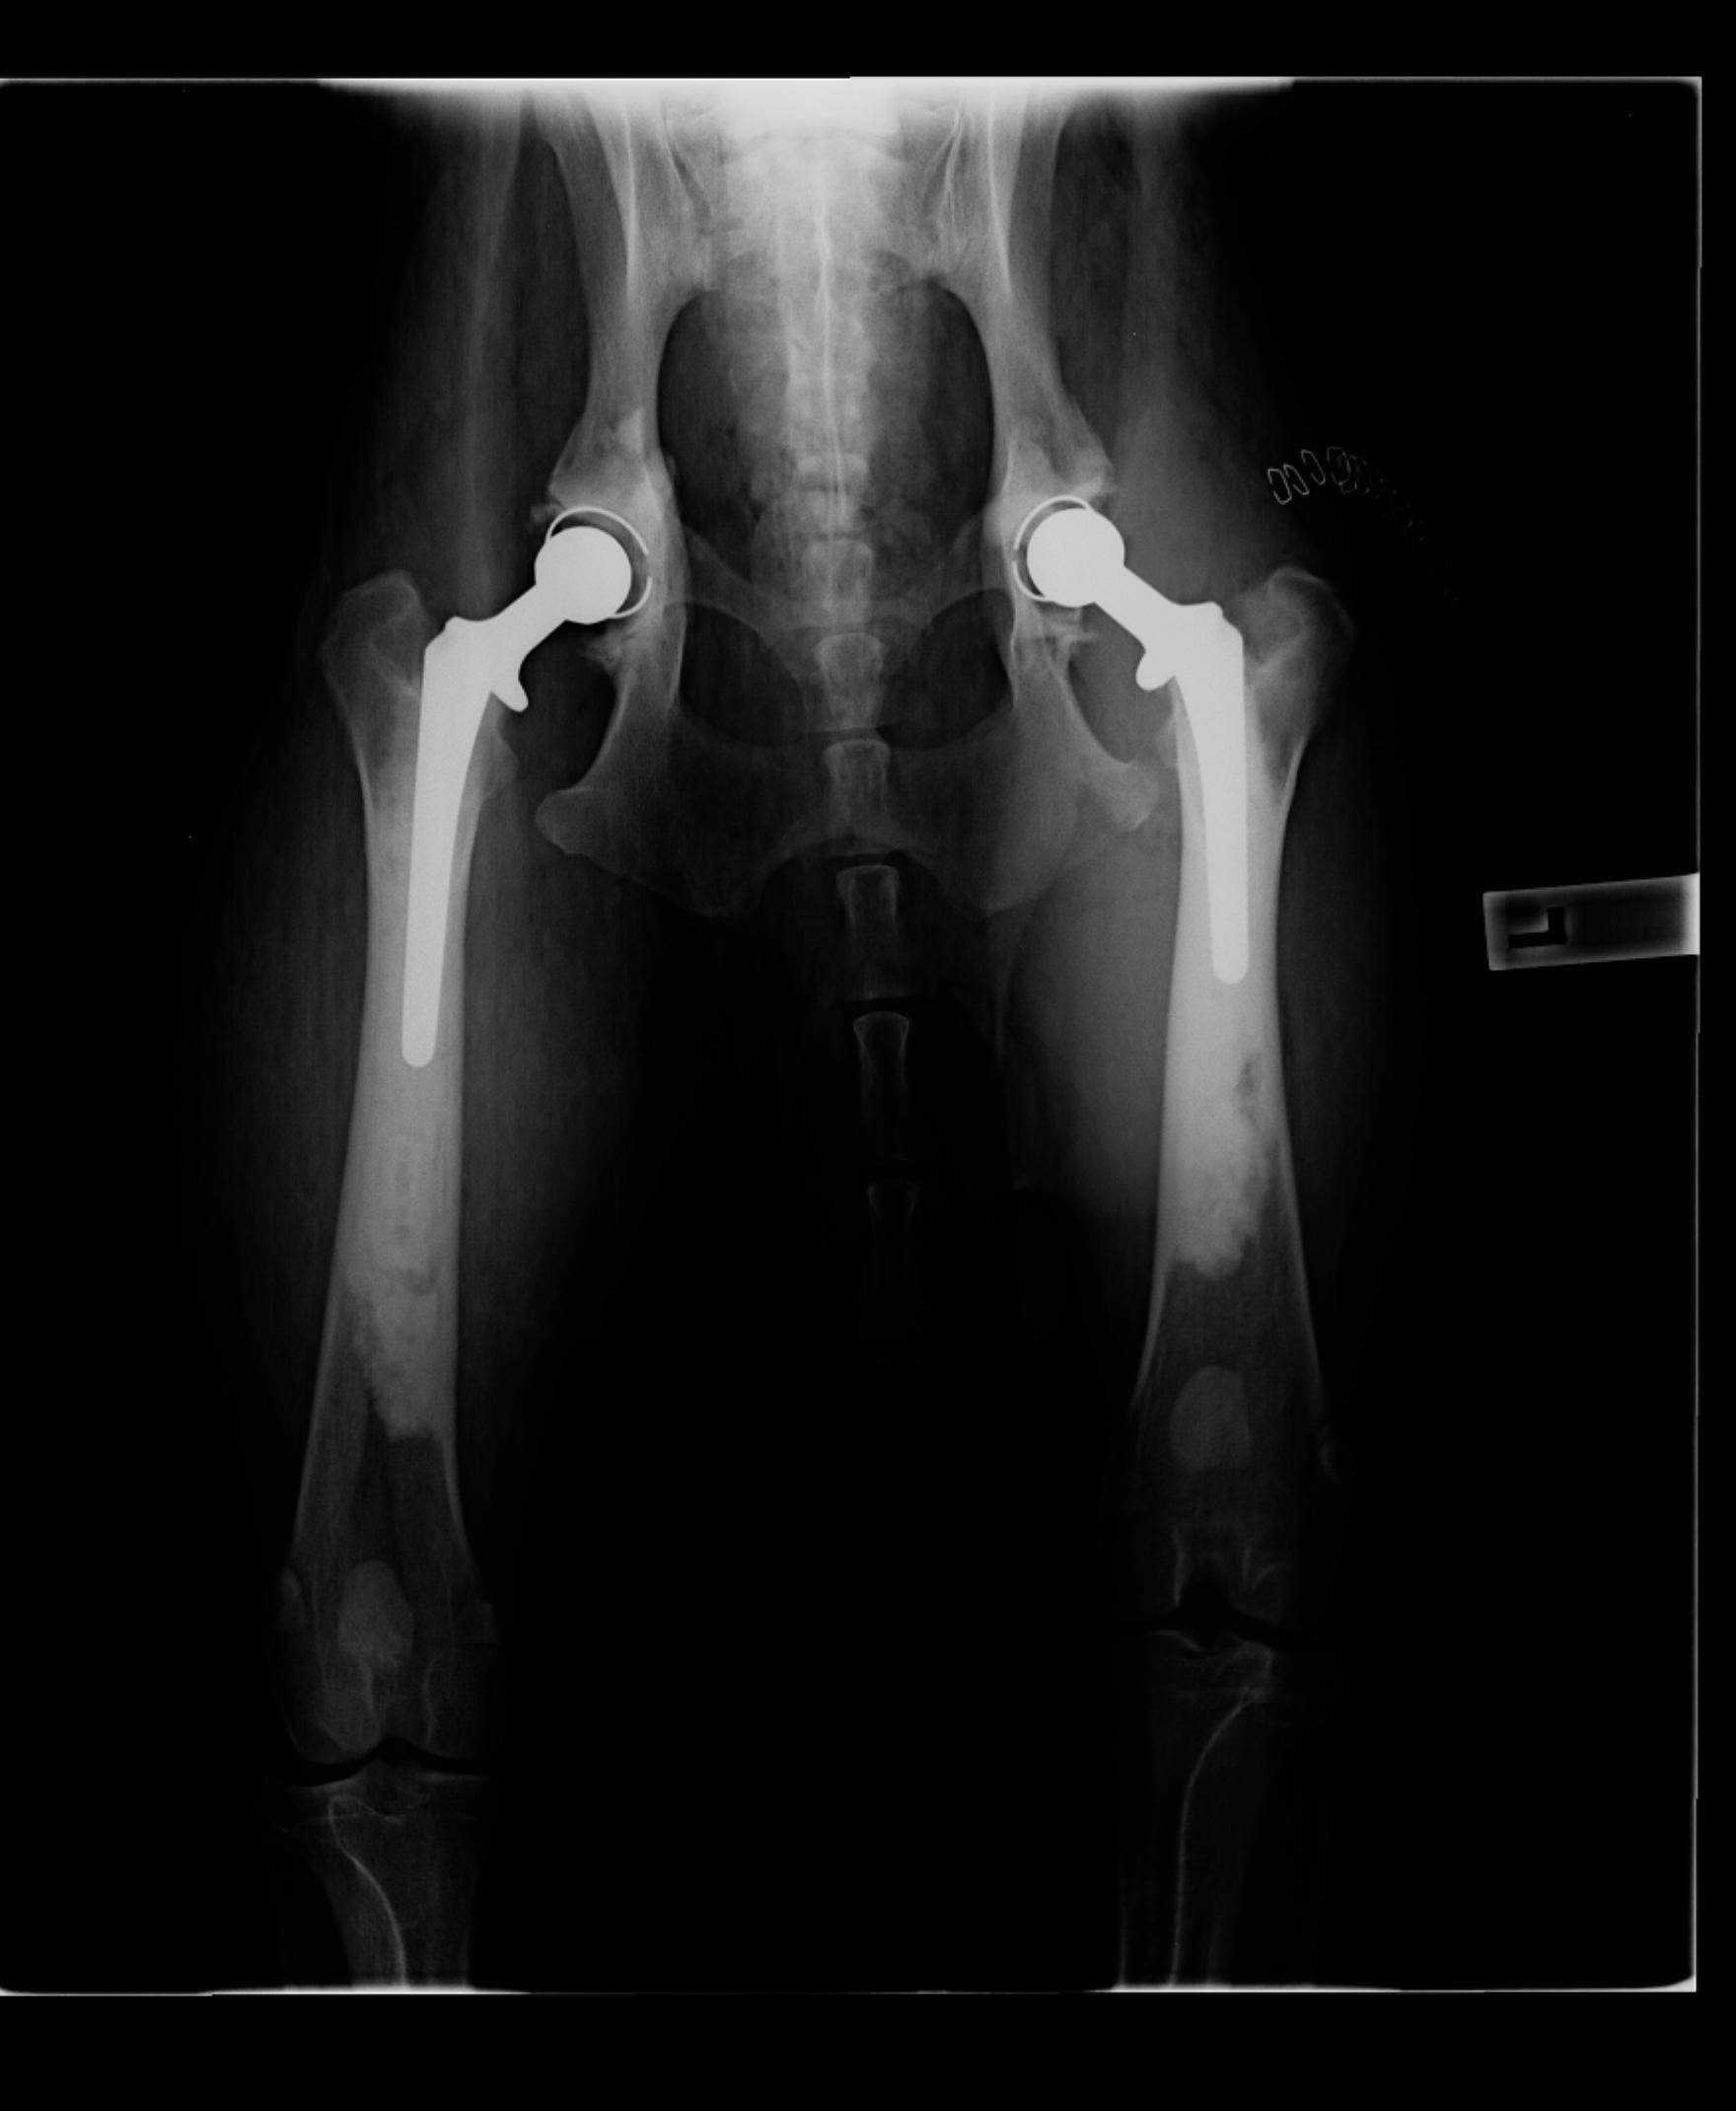

bianca.a Posted May 21, 2014 Author Share Posted May 21, 2014 Oh thank you all so very much ((hugs)) Well the surgeon is happy so I am happy! When I call tomorrow I am going to ask how his skin is. But here is his post op xray.....bionic boy! Link to comment Share on other sites More sharing options...

BC Crazy Posted May 21, 2014 Share Posted May 21, 2014 Cooper has pic perfect hips now :) do hope he can come home very soon Bianca & he makes a full speedy recovery. Link to comment Share on other sites More sharing options...